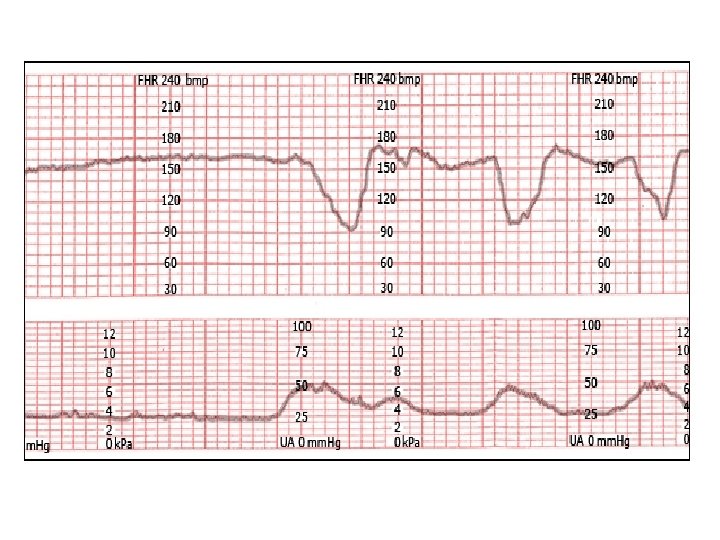

variable decelerations with absent to minimal variability

Variable decelerations with minimal to absent variability